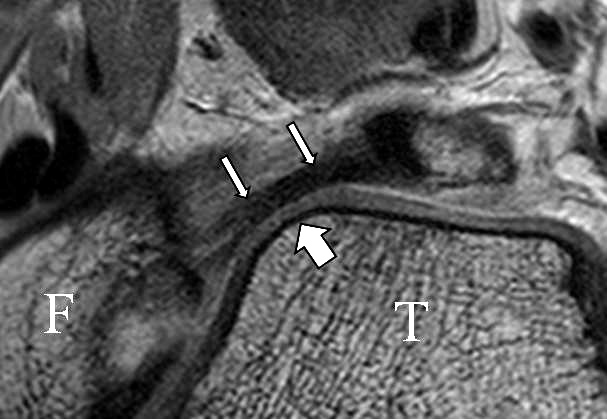

Das Ligamentum fibulotalare anterius entspricht einer bifaszikulären Struktur (Abb. 2 a) mit interponierendem fibrovaskulärem Gewebe (S. K. Sarrafian (ed). 2003). Es gibt jedoch Variationen der Ligamentanatomie. In 55% liegt das LFTA als bifaszikuläres Band (Abb. 2 a), in 9% als monofaszikuläre Bandstruktur (Abb. 2 b) und in 36% als multifaszikuläre, striäre Variante (Abb. 2 c) vor 3.

PD fs HR axial. Klare Darstellung eines filigranen, knapp über 1 mm breiten LFTA (Pfeil). Fibula (F).

Abbildung 3

Das LFTA verbindet die antero-inferiore Fibulaspitze mit dem Processus lateralis tali und inseriert hier an einem oder zwei kleinen Tuberkeln 3. Der in Neutralposition horizontale Verlauf erleichtert die kernspintomographische Darstellung in dieser Standardebene. Das LFTA weist durchschnittlich eine Breite von knapp über 2 mm auf 4. Somit sind bei einer Routinedarstellung in 3 mm Schichtdicke Anschnittsphänomene, die die Diagnostik erschweren, regelmäßig anzutreffen. Dementsprechend sind auch die ligamentären Subfaszikel nicht zu differenzieren. In koronarer Darstellung ist dies aufgrund der hohen Auflösung in der Schichtebene jedoch möglich (Abb. 2 a-c), wobei hier wiederum eine Integritätsbeurteilung des Bandes erschwert ist. Unter Verwendung hochauflösender Techniken im Millimeterbereich (Schichtdicke) sind hingegen auch in der axialen Ebene die subfaszikulären Strukturen zu beurteilen (Abb. 3).